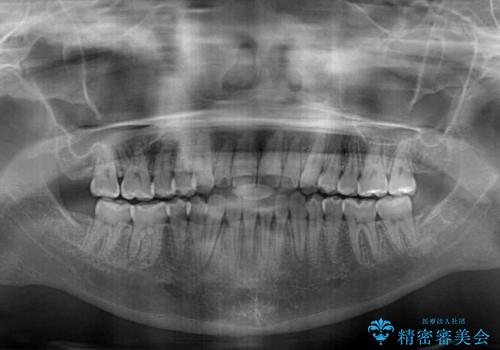

- 前歯のデコボコと、下顎の変位と受け口を気にして来院された患者様です。

初診時には大学病院にて顎の骨を切る外科矯正を勧めましたが、妥協的なゴールでも構わないので外科処置をせずに矯正を行いたいとのことでした。

まずは急速拡大装置にて上顎骨を側方に拡大し、インビザラインにて歯列と咬合を整えることとしました。

上顎骨を拡大したことで、下顎の歯列を上顎が受け入れられるようになりましたが、インビザラインでは咬み合わせを改善させることができなかったため、ワイヤー矯正にて仕上げることとしました。

ワイヤーを使用したものの、上下前歯のオープンバイトがなかなか改善されませんでしたが、患者希望により治療終了となりました。